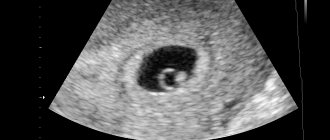

Трансвагинальное УЗИ (ТВУЗИ) — это исследование ультразвуком, проводимое специальным датчиком через влагалище. Такая методика позволяет более точно и детально вывести на монитор изображение матки с развивающимся в ней эмбрионом, шейки матки и яичников. При использовании вагинального датчика беременность будет видна гораздо раньше, чем при обычном скрининговом исследовании. Благодаря хорошей визуализации, такая методика является одной из основных для диагностики плода и своевременного обнаружения его возможных отклонений.

• Диагностики беременности

• Контроля за беременностью (только в первом триместре)